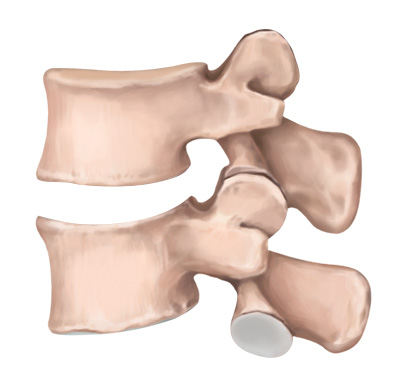

STEP 01

손상된 디스크

STEP 02

손상된 디스크 제거

STEP 03

인공디스크 삽입